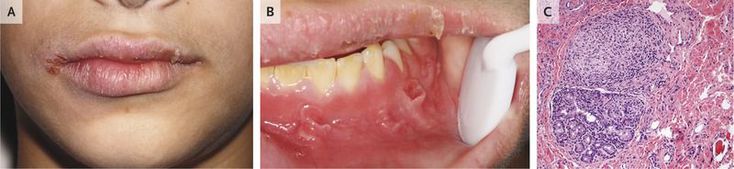

A 13-year-old boy presented with a 9-month history of episodic unilateral swelling of the face and oral pain. He reported having loose, nonbloody stools. Physical examination revealed asymmetric swelling of the face and lips with perpendicular fissuring (Panel A), and intraoral examination revealed discrete gingival erythematous hyperplasia and epulis fissuratum–like soft-tissue tags in the mucobuccal fold (Panel B). Granulomatous inflammation consistent with Crohn’s disease was found on histopathological examination (Panel C), and the patient was referred to a pediatric gastroenterologist. He was found to have tenderness to palpation in the right lower quadrant and periumbilical region, a rectal fissure, and painless rectal skin tags. Colonic biopsies showed chronic active colitis that was most prominent in the cecum and ascending colon, which confirmed a diagnosis of Crohn’s disease. Therapy with mesalamine and prednisone was initiated and slowly tapered. Maintenance of remission was achieved with mercaptopurine. The oral lesions slowly resolved over a 1-year period. At a follow-up visit 2 years after the initial presentation, the patient remained asymptomatic.